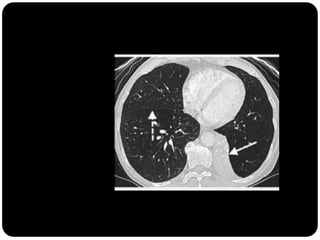

Atelectasia

 Diminuição de volume do segmento, deslocamento de uma ou mais

fissuras interlobares em direção à parte atelectasiada, desvio do mediastino

para o lado envolvido, deslocamento hilar, estreitamento dos espaços

intercostais e hiperinsuflação dos outros lobos / segmentos não atelectasiados